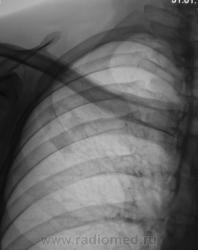

Я бы остановилась на множественных туберкулемах s1-2 обоих легких,Туберкулемы не однородны.за счет уплотнения,пл очаги.фиброз.

Слева туберкулома и корень подтянут Справа-очаги отсева .Динамика типичная- лечим.лечим-а туберкуломе хоть бы хны!

Туберкулёма только в С1+2 слева, как дела давно минувших дней.  Произошла реактивация туберкулёзного процесса с развитием двустороннего очагового туберкулёза. Имеется положительная динамика в виду некоторого уплотнения очагов. Таково мое мнение.